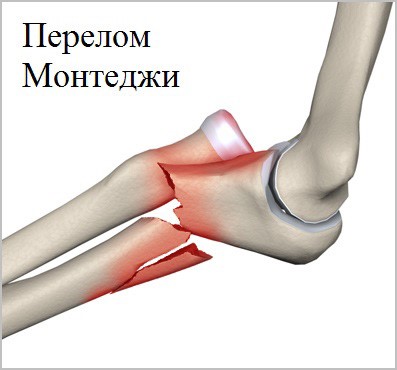

Также существует особая группа повреждений костей предплечья, которая в медицинской литературе называют переломо-вывихи Монтеджи и Галеацци. При этих повреждениях перелом локтевой сочетается с вывихом лучевой кости в локтевом суставе или наоборот перелом лучевой кости сочетается с вывихом локтевой кости в области лучезапястного сустава. Подобные повреждения обусловлены особой анатомией и пространственным расположением костей предплечья.